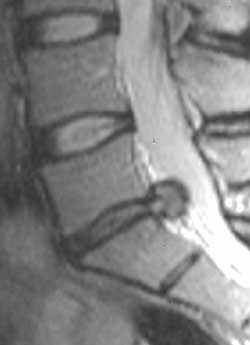

МРТ диагностика дегенеративных изменений позвоночника.

Рис. 3. Большая грыжа межпозвонкового диска L5-S1. Сагитальное изображение.